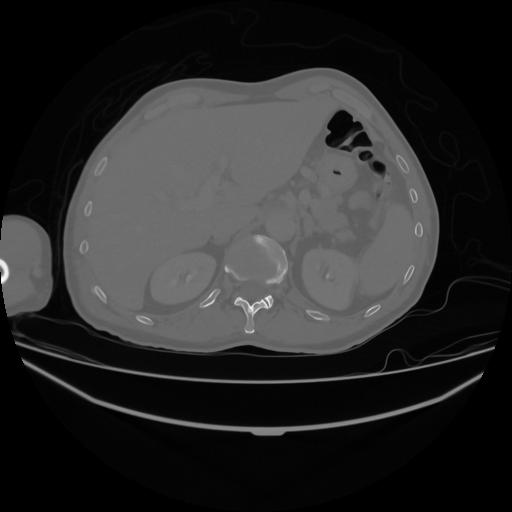

5 CUERPO,CE,Vol,1.0,CUERPO,,